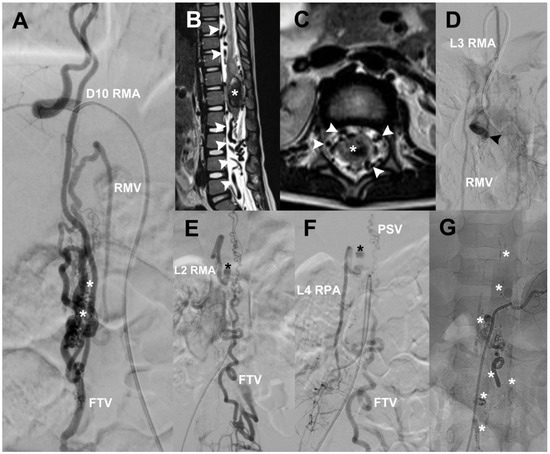

3.5.5. Case 11

| Case 11 | 5/M | Acute myelopathy, hematomyelia, paraplegia, sphincter incontinence, and lumbar pain | 4 | Conus medullaris diffuse AVM | Right D10 and L2 RMA, left L3 RMA, right L4 RPA | Diffuse nidus with various high-flow fistulas | Arterial aneurysm at right L2 and venous aneurysm at left L2 | Venous drainage runs to radiculomedullary veins and filum terminale vein | Embolized with Histoacryl (2 sessions), laminoplasty with partial resection of AVM, and hematoma evacuation | There is no evidence of AVM, clinical improvement, still with paraparesis (4/5) | 2 |